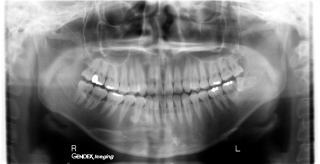

全顎エックス線診査→(下の写真)

※50歳以降の女性には骨粗しょう症の予備判定をおこないます。